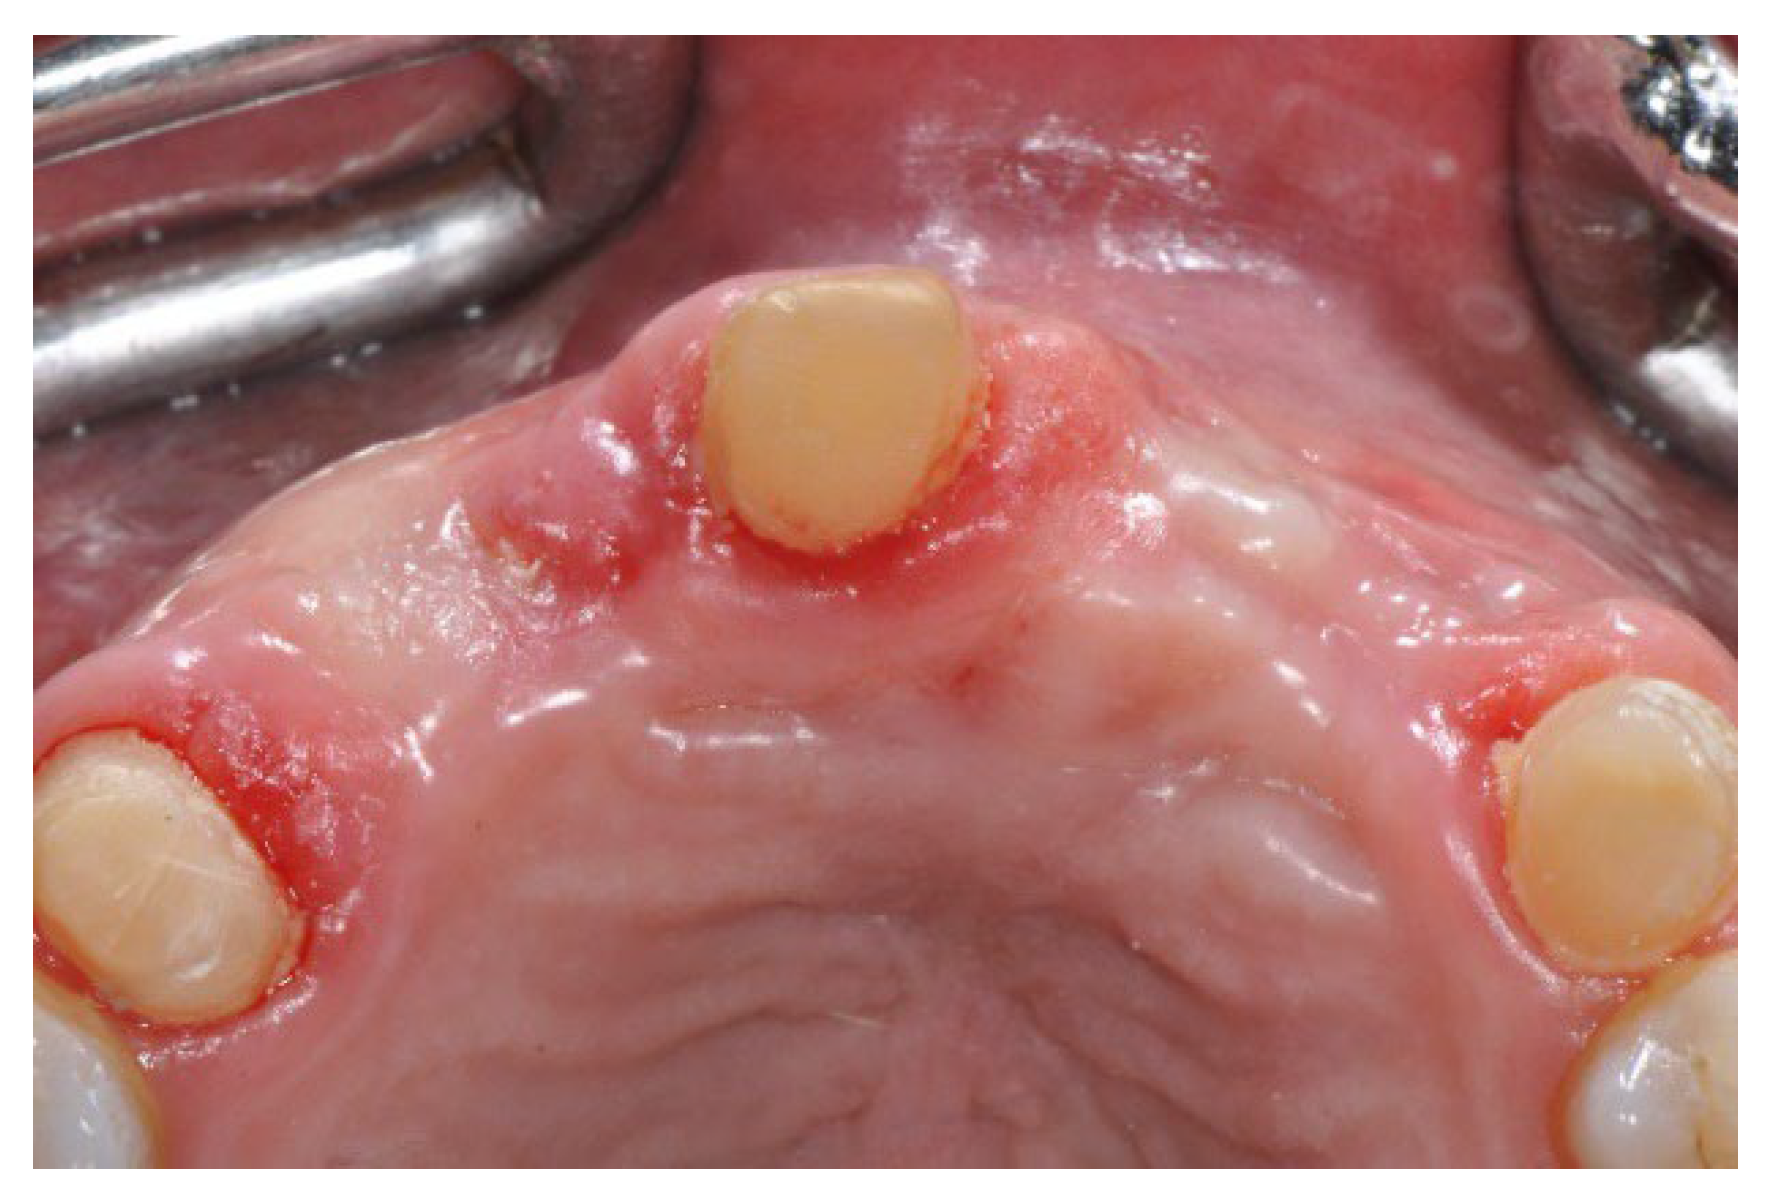

2.2. Surgical Procedure